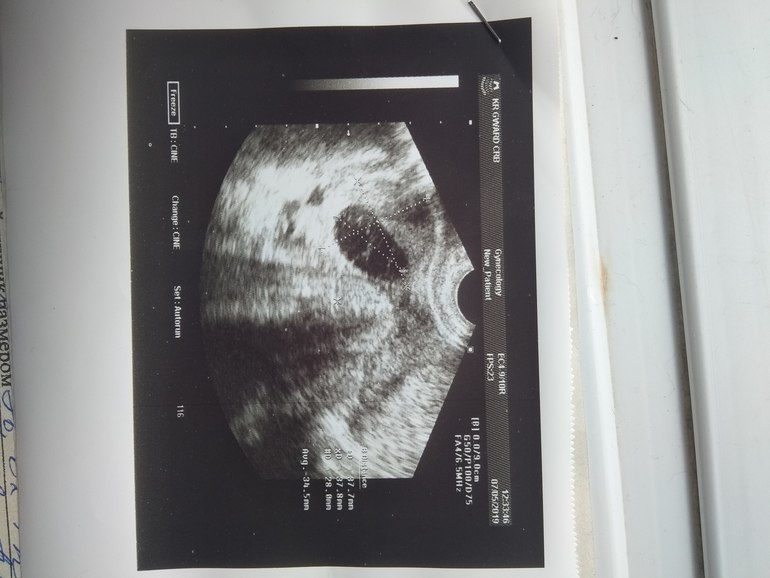

Беременность малого срока или замершая?

Убирайте слезы. Все наверняка хорошо. Видимо овуляция была раньше. Ждите ХГЧ и не паникуйте. Шикарный эндометрий, ПЯ в матке - это уже очень даже хорошо.

Другого УЗИ в нашей дыре к сожалению нет,хотя врача все хвалят этого.Просто один его вывод замершая или нормальная...и тесты пустые

Здесь не то что другое узи, а смотреть динамику нужно. Сделайте узи там же через недельку только. ХГЧ - один результат тоже ничего не даст, тоже нужно минимум 2, чтобы увидеть динамику. А плакать не нужно! Зачем вам лишние переживания! Отдыхайте и в пн вперед за хгч и на Узи )

Эндометрий, яичники, пя- ничего не по пойму. Фолликулометрия 11 ДЦ.